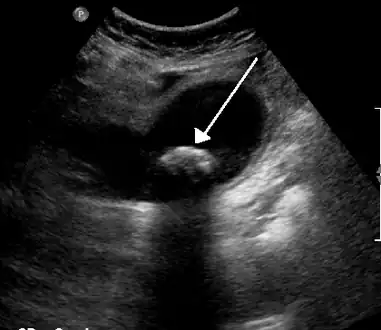

Diagnosis is typically confirmed by abdominal ultrasound. Other imaging techniques used are ERCP and MRCP. Gallstone complications may be detected on blood tests.[2]

On abdominal ultrasound, sinking gallstones usually have posterior acoustic shadowing. In floating gallstones, reverberation echoes (or comet-tail artifact) is seen instead in a clinical condition called adenomyomatosis. Another sign is wall-echo-shadow (WES) triad (or double-arc shadow) which is also characteristic of gallstones.[43]